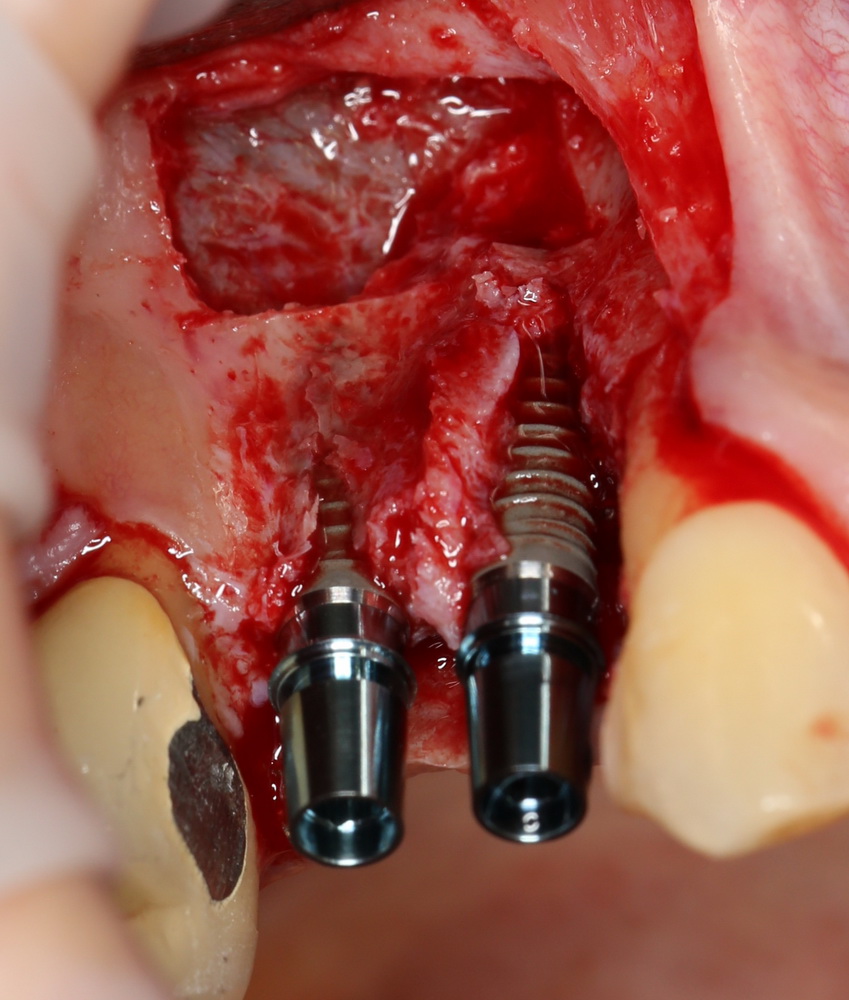

Синуслифтинг и имплантация

Конечная цель операции синуслифтинга – создание адекватных условий для установки имплантов. При этом, нередко удается провести имплантацию одновременно с операцией синуслифтинга. Как уже говорилось выше, это возможно, если существующий объем костной ткани позволяет стабилизировать имплантат заданного размера (рис 43, 44, 45):

Рисунок 43, 44, 45. Установка имплантов одномоментно с операцией синуслифтинга: слева – этап синуслифтинга, в центре – подготовка лунки под имплантат (виден спейсер и слизистая оболочка гайморовой пазухи), справа – установленный имплант